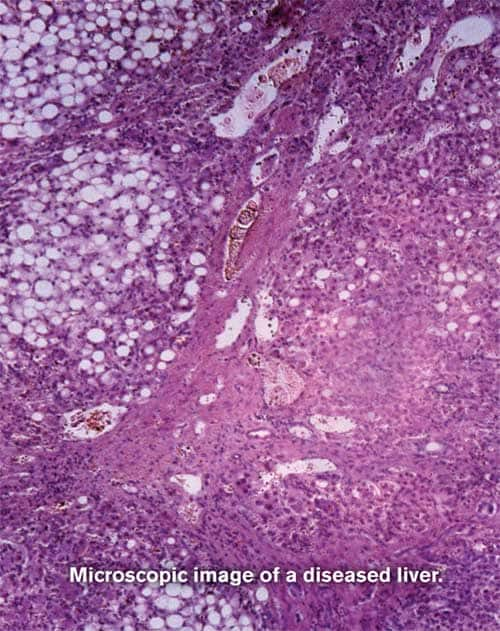

Most people associate liver damage with alcohol abuse or hepatitis. Yet a stealth liver condition of epidemic proportions lurks in this country that may pose an even greater threat to the public health. Roughly one-third of the American population1-3 suffers from nonalcoholic fatty liver disease or NAFLD. Many of its victims don’t know they have it. NAFLD can go undetected for years and may eventually progress to inflammation and scarring of the liver (cirrhosis) and, in some cases, full-blown liver failure. A formerly rare condition, its rapid emergence has been linked to skyrocketing rates of metabolic syndrome3-5 and “diabesity,” the term many experts use for co-occurring diabetes and obesity. While poor dietary choices are often to blame, cutting-edge research suggests that hidden genetic factors may also play a role, as some people do not metabolize polyunsaturated fats properly, resulting in fatty deposits in the liver.6 As mainstream medicine continues to struggle in the search for drugs to manage this widespread condition, emerging scientific evidence has shed light on effective natural interventions that may halt or even reverse its progress. In this article, you will learn about NAFLD and its impact on overall health in aging individuals, along with the various stages of the condition, ranging from barely detectable indicators to cirrhosis and liver failure. You will also discover compelling evidence for seven potent interventions that may effectively combat this challenging and widespread disease. Fat Overload, Liver Damage, and the Inflammatory Storm

NAFLD (nonalcoholic fatty liver disease) is defined as deposition of fat in the liver cells of patients with minimal or no alcohol intake and with no other known cause.7 The term “NAFLD” refers to a group of related and progressive conditions closely associated with overweight and obesity.2 NAFLD starts off as a low-level disturbance characterized by dull right upper-quadrant abdominal discomfort and fatigue in most patients, but it is hardly benign.8 Early NAFLD can ultimately progress to a more serious condition, nonalcoholic steatohepatitis or NASH.9 About a third of people with NAFLD will develop NASH.8 And about 20% of people with NASH will go on to liver fibrosis and cirrhosis, with its accompanying risk of liver failure and even liver cancer.2,8,10 Overall, people with NAFLD stand a 12% increased risk of liver-related death over 10 years.8 As the prevalence of overweight and obesity rises, so do the rates of NAFLD, NASH, and their end-stage consequences. Together, these conditions affect roughly 30% of US adults and, shockingly, up to 10% of our children.2 NAFLD has multiple interrelated causes. Primary mechanisms include obesity leading to steadily increasing insulin resistance coupled with an overabundance of circulating fatty acids. These factors fuel one another in a destructive cycle.4 Together with the recently-recognized role of advanced glycation end-products (AGEs), these events lead to increased oxidant stress and ultimately inflammation, cell death, and fibrous destruction of liver tissue.3,4,8 An overload of fatty acids and abnormal lipid profiles factor so heavily in the onset of NAFLD that they’re now referred to as “lipotoxicity” because of the ways they directly poison liver tissue.9,11,12 And as fat builds inside liver cells, they begin churning out a storm of fat-related cytokines known as adipokines, which fan the inflammatory flames of the metabolic syndrome and NAFLD.1 Unfortunately, despite a growing understanding of what goes wrong in NAFLD, scientists have been persistently baffled in their attempts to prevent and treat it with drug therapies. Lifestyle interventions such as steady, gentle weight loss and regular exercise have been the only interventions that offered any hope at all.2,9 Insulin-sensitizing drugs, while theoretically of value, have proved disappointing in clinical trials. The only successful pharmaceutical intervention for dealing with NAFLD has been metformin, which will be examined below. Cholesterol-lowering drugs like statins have no proven benefit to date.4 Further studies are needed to determine if bariatric surgery to induce weight loss benefits patients with NAFLD.9,13 Given the nutritional origins of NAFLD, it comes as no surprise that a handful of nutrients with targeted antioxidant, anti-inflammatory, and metabolic properties have emerged in recent years as the most promising preventive therapies. A recent clinical trial of vitamin E versus the prescription drug pioglitazone (Actos®) provided some compelling results, and serves as an excellent introduction to a broader examination of the most promising, safe, low-cost interventions. 7 Interventions to Heal and Protect Your LiverVitamin ELiver scientists at the Virginia Commonwealth University Medical Center began a series of studies on NASH (the advanced middle stage of NAFLD) and vitamin E in 2004. Based on their knowledge that NASH arises from persistent insulin resistance and oxidative stress, they examined the effects of pioglitazone (Actos®), an insulin-sensitizing drug, and vitamin E.14 Their initial hypothesis was naturally that the combination of vitamin E plus the drug would produce greater benefits than vitamin E alone. And indeed, looking at liver biopsies that seemed to be the case. Patients receiving both vitamin E (400 IU per day) and pioglitazone (30 mg per day) had improvements in more parameters than did patients on vitamin E alone (though the vitamin E patients did show some improvement).14 Encouraged (and curious), the researchers designed an additional trial aimed at evaluating the effects of vitamin E and pioglitazone independently in patients with NASH.15 In this study, published in mid-2010, subjects received either vitamin E (800 IU per day) or pioglitazone (30 mg per day), or placebo, for 96 weeks.16 The results were surprising, to say the least. Only vitamin E, and not pioglitazone, produced significant improvements in the appearance of liver tissue on biopsies.16 Both treatments improved levels of liver cell-injury markers in blood, and both reduced liver fat levels and inflammation. This study showed that vitamin E, formerly thought to be additional therapy for NASH, was actually superior to pioglitazone at improving liver damage. Let’s now look at some clues that might have predicted these otherwise startling results, based on what was already known about vitamin E in liver disease. Vitamin E is a powerful antioxidant, and hence an obvious choice once the role of oxidant stress was made clear in NAFLD.17 We had known since at least 1992 that people with fatty liver disease and NASH had depressed levels of vitamin E in their blood, the result of that increased oxidation.18,19 By the beginning of this century, relatively low-dose vitamin E (450 IU/day) was shown to reduce circulating liver enzymes, a chemical marker of liver cell injury.20,21 Clinical trials of combination antioxidants, including one with silybin (milk thistle) and phospholipids showed good results at improving insulin resistance and reducing markers of liver cell fibrosis (a finding in advanced liver disease).22,23 In patients receiving vitamin E 1,200 IU mg per day, overall fasting glucose levels improved while markers of liver cell damage decreased.24 In a subgroup of those patients, there was evidence of reduced inflammation and improved expression of PPAR-alpha, a vital metabolic sensor complex, providing evidence of new and separate mechanisms of action. Important animal studies began to appear around 2009 that refined our understanding of how vitamin E works. One study provided the first evidence that vitamin E can prevent NAFLD before it develops, largely by reducing oxidative stress, inflammation, and liver cell death by apoptosis.25 Another study demonstrated a vitamin E-related reduction in oxidative damage and tissue levels of the inflammatory mediator TNF-alpha, while beneficially reducing PPAR-gamma activity.26 This wealth of animal and now human data clearly supports daily use of 800-1,200 IU of vitamin E for prevention and treatment of NAFLD and NASH. Let’s look at the other nutrients known to be helpful in preventing this troubling suite of conditions. This wealth of animal and now human data clearly supports daily use of 800-1,200 IU of vitamin E for prevention and treatment of NAFLD and NASH.